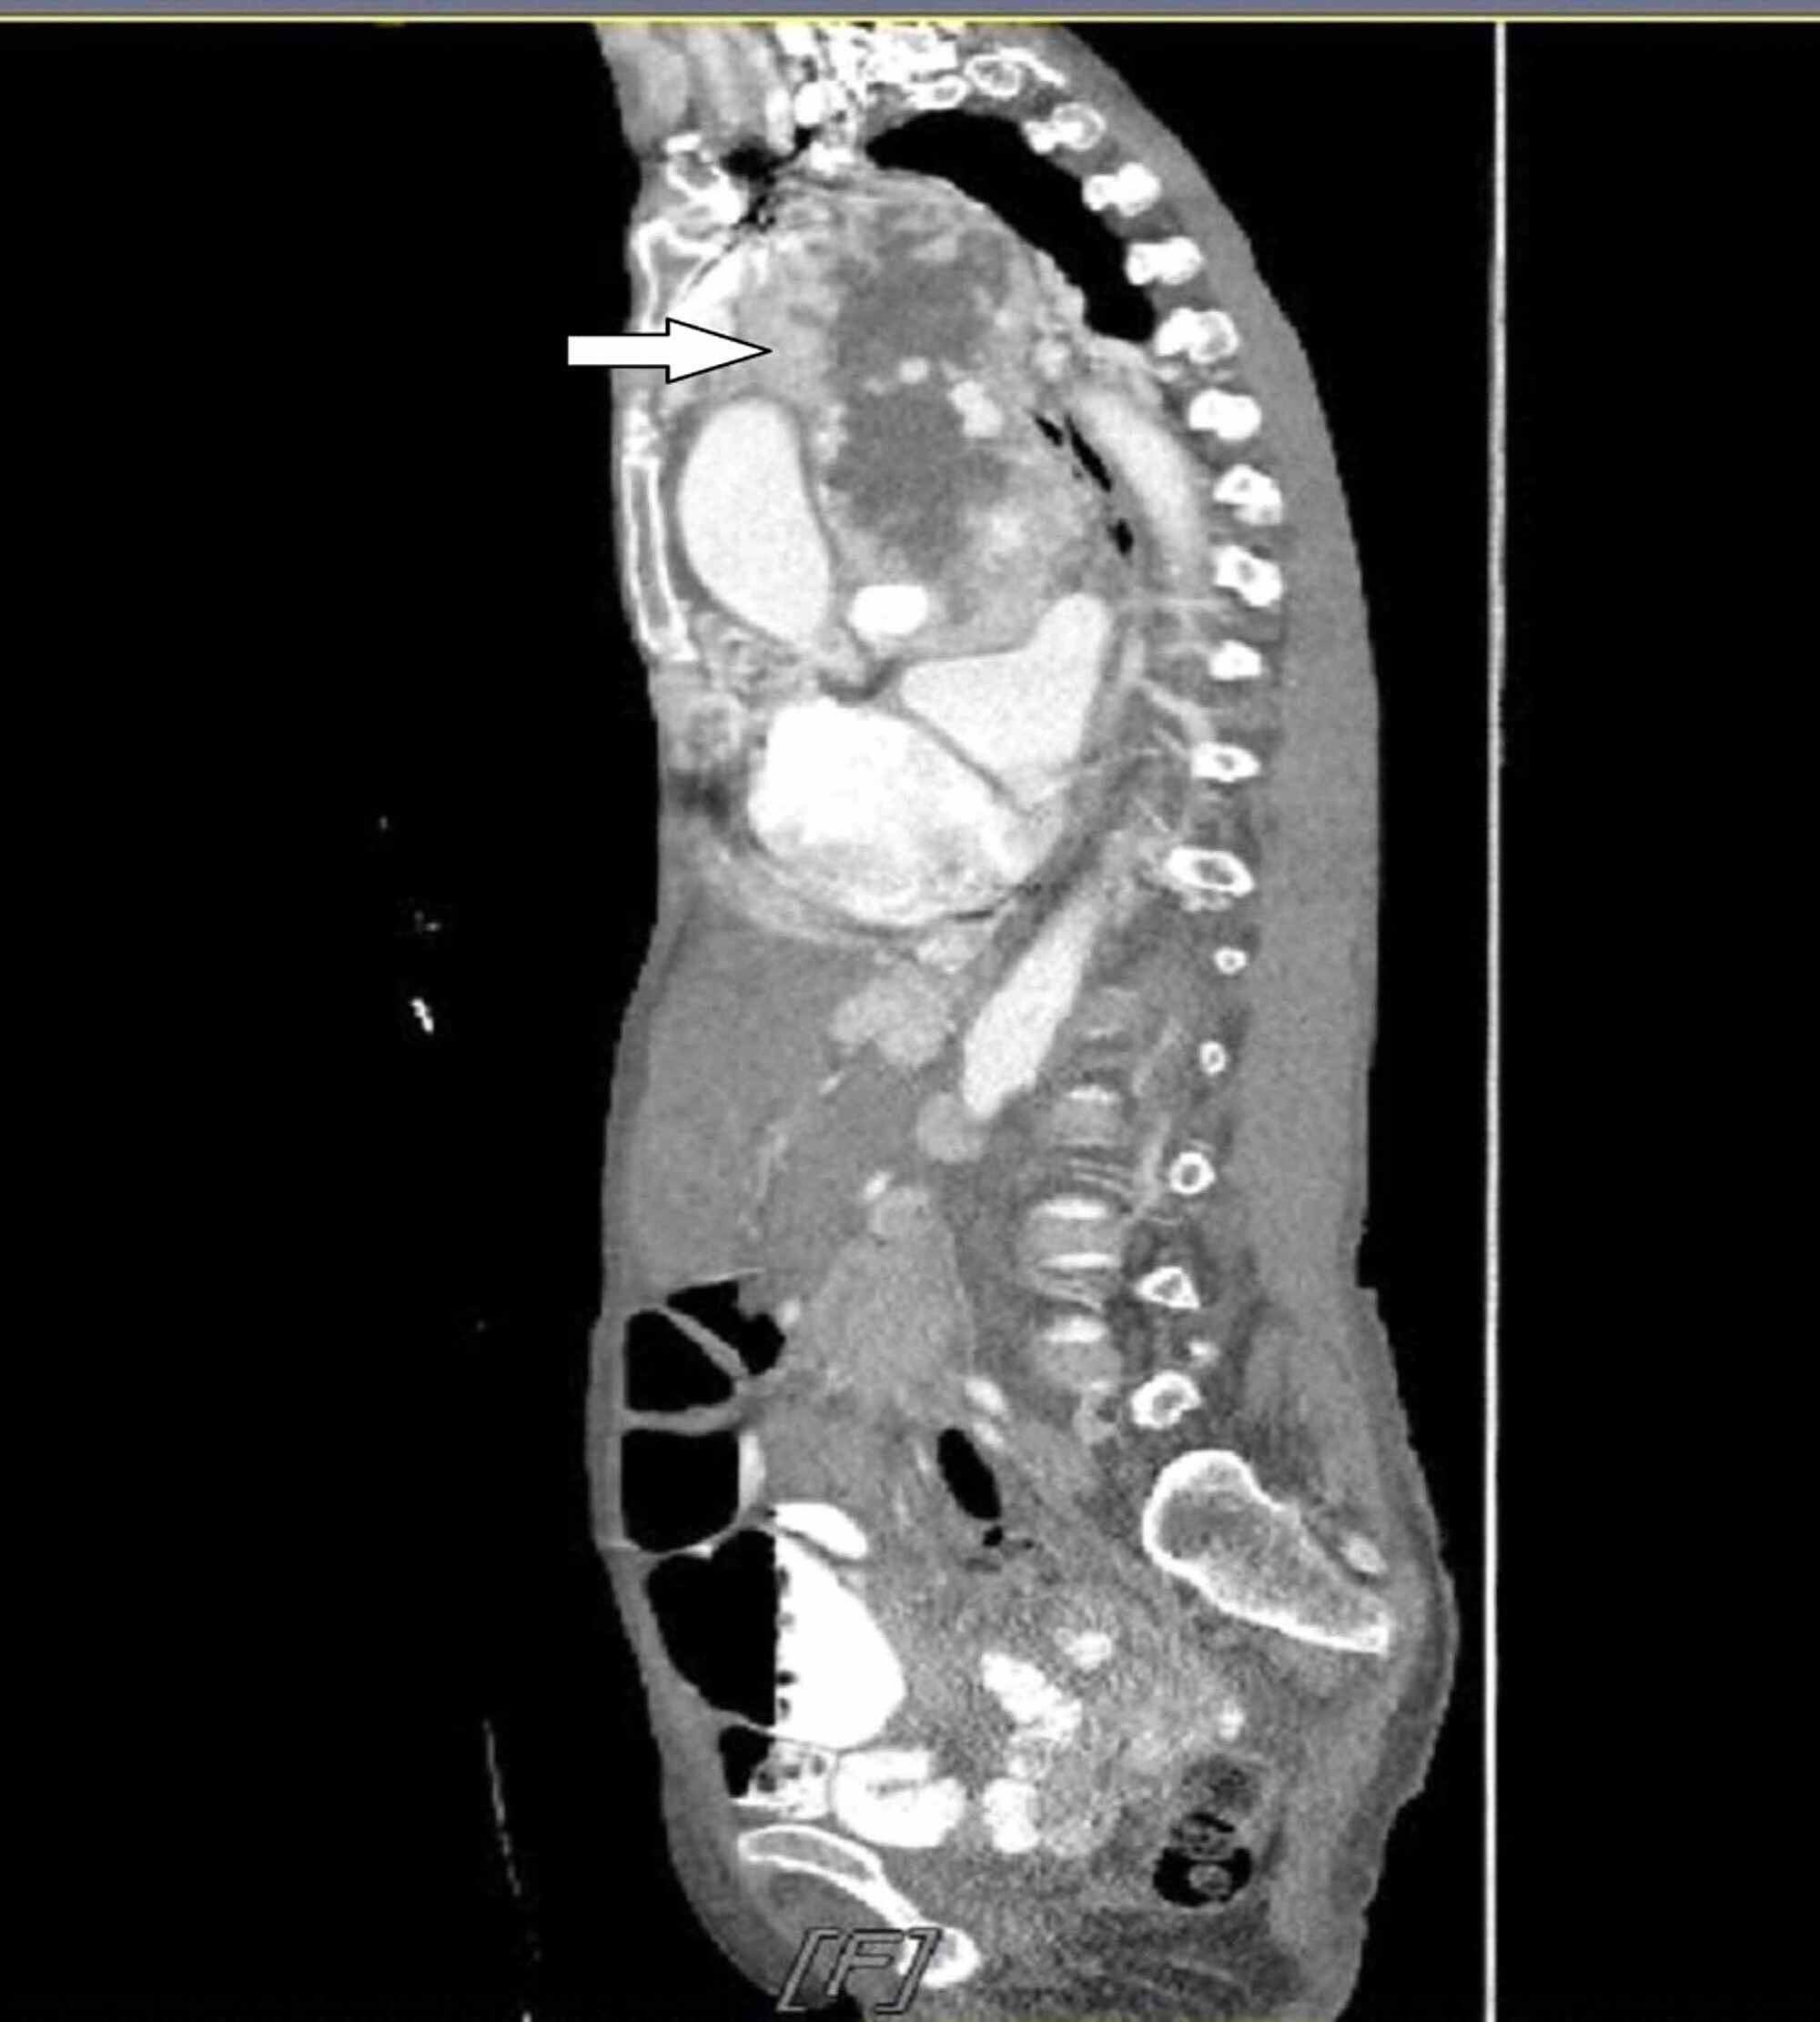

Baseline imaging of the primary thymic neuroendocrine tumor. CT axial Thymic Neuroendocrine Tumor Although clinical and molecular data are sparse, their general. The latest world health organization (who) classification from 2015 has grouped lung and thymic neuroendocrine tumours (nets) (named neoplasm in the digestive who classification) within one unique group but confirmed their subdivision into four main categories: Primary neuroendocrine tumors of the thymus (netts) are rare and biologically. Thymic neuroendocrine tumors (nets). Thymic Neuroendocrine Tumor.